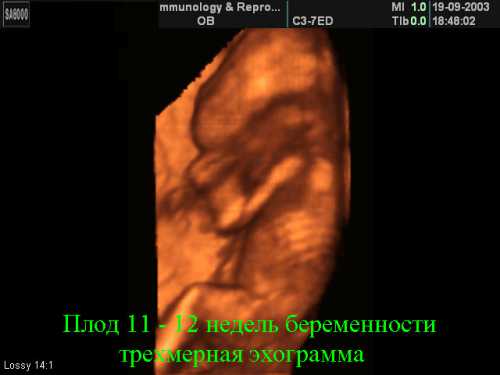

Размер плода на неделе беременности примерно составляет см. С приходом недели мамочки могут вздохнуть с облегчением, так как это означает не только завершение утренних недомоганий в виде тошноты и рвоты, но и снижение риска самопроизвольного аборта, поскольку выкидыши случаются, в основном, до недели. К тому же у женщины появляется возможность самостоятельно прослушивать сердцебиение своего малыша. Живот на неделе беременности начинает потихоньку расти. Теперь матка еще больше увеличилась в размерах, изза чего незначительно приподнялась вверх в брюшную полость. Сама матка весьма эластична, благодаря чему во время беременности может растягиваться и увеличиваться в объеме до раз, а уже через месяца после родов что является сравнительно коротким промежутком времени способна возвратиться в свое привычное состояние. При ультра звуковом обследовании на неделе врач гинеколог может предположительно, но уже с большей точностью, определить дату предстоящих родов. А пока что сердцебиение мамочки заметно учащается, и постепенно наливается грудь, доставляя дискомфортные ощущения в виде небольшой тяжести. Характерным для недели беременности считается появление гипер пигментации кожи у будущих мам. Так, на животе беременной женщины может появиться темно коричневая продольная полоска. Пигментные пятна могут проявиться на лице, шее и в области подмышек, причем их размеры могут быть абсолютно разными, но не волнуйтесь, после беременности они исчезнут. В сосудах беременных женщин также происходят некоторые изменения, которые проявляются в виде красных или синеватых звездочек, выступающих на поверхности кожи, чаще всего на руках, лице, шее и груди. Но это все временно, и после родов они самоуст ранятся. Если возникли боли на неделе беременности, то непременно следует обратиться к профессиональным врачам, причем немедленно. Возможно, что именно неделя станет началом периодической изжоги, которая появляется изза выработки плацентой гормона прогестерона, который, в свою очередь, ослабляет перегородку между желудком и пищеводом, и желудочный сок может путешествовать по пищеводу, вызывая чувство жжения. Конечно, у большинства беременных женщин проблема изжоги имеет серьезное место на более поздних сроках, в результате оказываемого давления матки на желудок. Поэтому если изжога появилась на неделе, то это еще не повод для повышенного внимания. Она еще проявит себя в третьем триместре с новой силойнеделя является рубежом первого и второго триместров беременности, и на этом рубеже чрезвычайно важно пройти первое плановое. УЗИ, поскольку именно сейчас можно будет выявить возможные врожденные пороки у плода и отклонения в его развитии, которые на более поздних сроках очень сложно зафиксировать, а порой совсем невозможно. Кроме того, при ультра звуковом обследовании врач может с точностью определить срок беременности, правда во избежание ошибки и дальнейших недоразумений в выписке. УЗИ указывается срок по зачатию и акушерский. Акушерство, беременность и роды система дневников для будущих и настоящих мам, интерактивный календарь брмнности, библиотка млдой мамы. Беременность в среднем продолжается дней, или акушерских месяцев, считая от первого дня последней менструации продолжительность акушерского месяца дней акушерских месяцев равняются неделям. В течение этого времени беременности из оплодотворенной яйцеклетки развивается зрелый плод, способный к внеутробному существованию. Приведенный ниже календарь беременности описывает этапы развития плода. В течение месяца недели происходит дробление зиготы, имплантация, образование зародыша, зачатков важнейших органов и зародышевых оболочек. В конце месяца недель длина плода см, тело его сформировано, имеются зачатки конечностей, головка равняется длине туловища, на ней заметны зачатки глаз, носа, рта, начинается формирование половых органов.

В конце месяца недель длина плода см, вес г, головка крупная, заметно различие в строении наружных половых органов, конечности совершают движения, видны пальцы рук и ног, в хрящевом зачатке скелета появляются первые точки окостенения. В конце месяца недель длина плода см, вес г, формируется лицо, происходит окостенение черепа, в основном заканчивается, формирование мышечной системы, движения конечностей становятся активнее, но матерью не воспринимаются, пол плода различается ясно. В конце месяца недель плод достигает длины см вес г. Кожа красная, покрывается пушковыми волосами. Сальные железы начинают выделять жировое вещество, которое смешивается с чешуйками эпидермиса и образует сыровидную смазку. В кишечнике образуется меконий. |